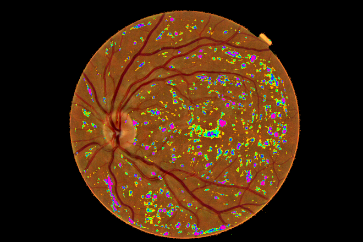

Refer to caption

Figure 4: Pixel probability maps obtained from the final CNN for a different number of epochs. In initial epochs, the probability map include low probabilities of MA (depicted as green spots), in the subsequent epochs, the medium and high probabilities are in blue and purple respectively.